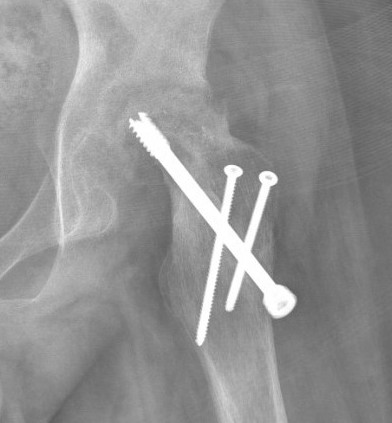

Options

Intertrochanteric

Base of Neck

Subcapital